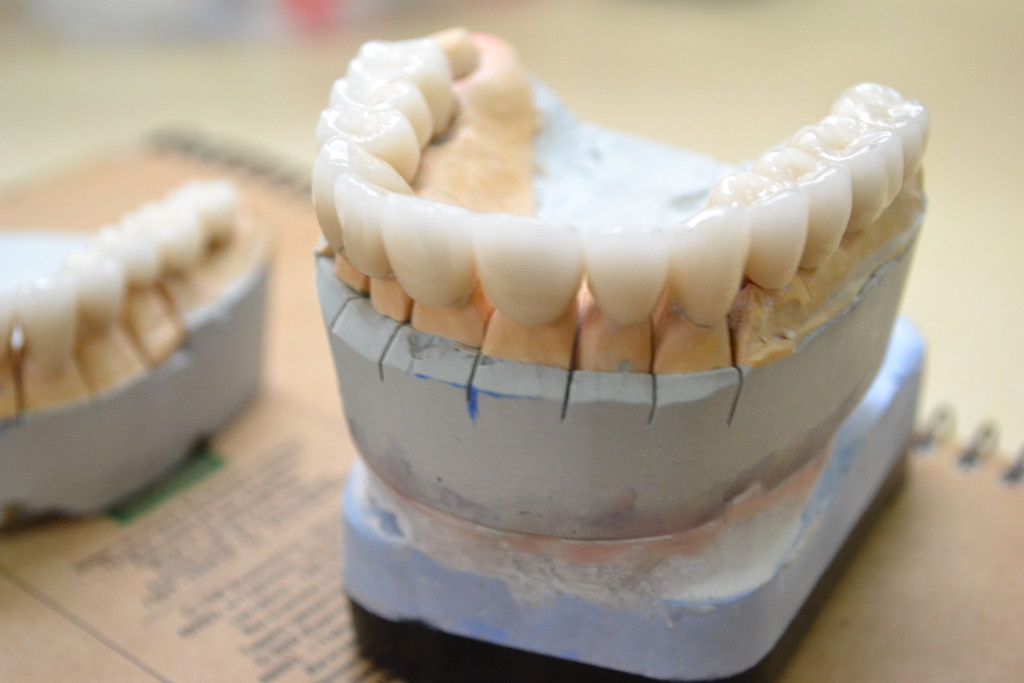

- изготовленные керамические коронки E-max